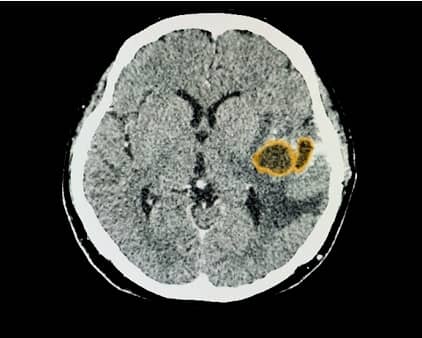

진단 검사

대상을 정확하게 파악하기 위해 컴퓨터 단층 촬영(CT)이나 자기 공명 영상(MRI) 등의 진단 검사를 실시합니다.